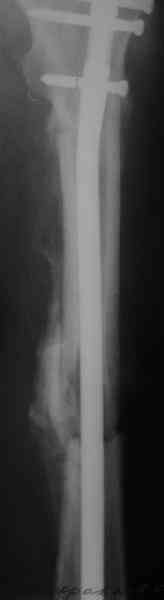

> денамизация - февраль 2006. ( 3 и 4 снимки) на сегодняшний день (снимок 5) беспокоит боли в тбс...

Судя по уровню перелома, винты в шейку избыточны, подойдет и диафизарный гвоздь. Все, что нужно, это тиски и труба. Загнуть сразу ниже отверстий градусов на 8-10, и вся недолга. Последние годы у нас это рутинная практика. Предызогнутые еще с завода гвозди неудобны тем, что они уже правый-левый.

Согласен, что 3,5 см укорочение этим снимкам не соответствует, за счет перелома и деформации - 1,5 см от силы. То есть либо ошибка измерения, либо приводящая контрактура, либо укорочение за счет другого отдела.

Согласен, что закрытый реостеосинтез с рассверливанием и коррекцией оси - это то, что надо. Мы бы ввели в центральный отломок статических 2-3 винта, и один динамический винт в дистальном отломке.